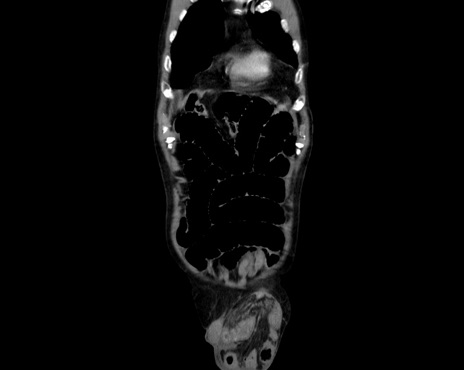

症例26(冠状断像)

【症例】80歳代男性

【主訴】嘔吐

【現病歴】昨晩2回嘔吐あり、今朝になっても嘔吐あり。来院。

【既往歴】胃潰瘍

【身体所見】意識清明、BT 37.6℃、BP 166/95mmHg、HR 100bpm、SpO2 97%、腹部:平坦・軟、腸蠕動音聴取良好、圧痛なし。

【データ】WBC 21900、CRP 1.4